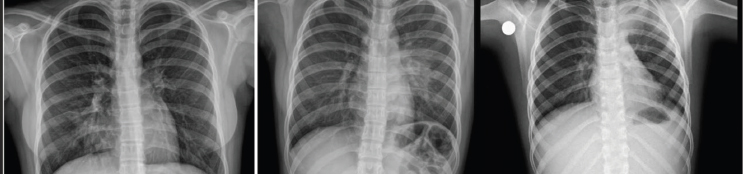

Respiratory findings were observed in 23% of patients, including crackles, wheezing, rhonchi, crepitations, reduced air entry and exit during inspiration and expiration, and decreased vesicular breath sounds on physical examination. Of these, isolated rhonchi, detected in 6 (26.1%) of the 23 patients, were the most common pulmonary finding. Chest X-rays were performed on 7% of the study population, revealing pneumonia in three (3) cases—one in the right lung and two in the left lung (Figure 2). One patient with left lung pneumonia also required a chest CT scan (Figure 3).

Figure 2. Pneumonia in the right lung (A) and in the left lung (B-C)